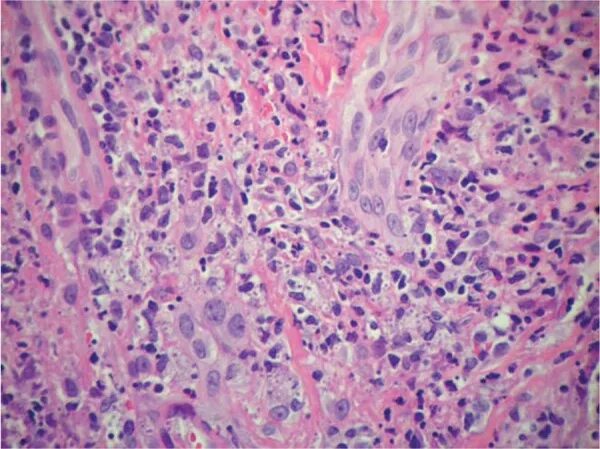

Гистоплазмоз это